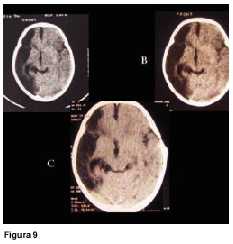

A los 3 meses de edad consultó por hemiplejia izquierda y retraso psicomotor. La tomografía computada (TC) de cráneo demostró un infarto hemisférico derecho (figura 1). Los estudios complementarios pusieron de manifiesto una coartación de aorta torácica descendente, sin evidencia de patología arterial sistémica. A nivel encefálico se estudió con angiografía de cuatro vasos de cuello, que demostró la existencia de una enfermedad de moyamoya (figuras 2 a 4). En ese momento no se consideró el tratamiento quirúrgico y una vez estabilizada se otorgó el alta. La coartación de la aorta no requirió cirugía y no se investigó el eventual nexo con la enfermedad de moyamoya. A los 8 meses de edad comenzó con hemiparesia derecha progresiva, lo que junto a su hemiplejia izquierda agravó su déficit motor severamente. Ingresó al Centro Hospitalario Pereira Rossell a los 10 meses. El examen del ingreso mostraba retardo neuropsíquico, hemiplejia izquierda espástica y hemiparesia derecha severa, que apenas vencía gravedad y no oponía resistencia. Una nueva TC mostró como elemento agregado al infarto derecho previo, una isquemia hemisférica izquierda (figura 5). Se resolvió realizar una revascularización quirúrgica del hemisferio izquierdo. Se intervino (figura 6) en el Servicio de Neurocirugía Pediátrica del Hospital. El procedimiento realizado fue una pialsinangiosis, con disección de la arteria temporal superficial izquierda con galea satélite y la sutura del tejido periarterial a la aracnoides temporal. La evolución posoperatoria fue buena, con recuperación progresiva de la función motora del hemicuerpo derecho. En forma gradual también comenzó a recuperar motricidad de su hemicuerpo izquierdo, anteriormente pléjico, y a mejorar sus performances, comenzando a pronunciar palabras a los cuatro meses, aunque manteniendo un retraso en el desarrollo psicomotor. Al año de operada se constató leve hemiparesia izquierda, ausencia de elementos deficitarios motores a derecha y persistencia de alteraciones en el lenguaje. Una ARM realizada a los diez meses de la operación mostró desarrollo de circulación colateral hacia el área quirúrgica (figura 7). Una TC de control permitió ver el infarto secuelar de hemisferio derecho y disminución franca de la hipodensidad del hemisferio izquierdo a los 18 meses de operada (figuras 8 y 9).

El resultado favorable de la técnica quedó efectivamente evidenciado en los estudios imagenológicos hechos 10 y 18 meses después de la cirugía, ya que la RM mostró desarrollo de circulación colateral hacia el área quirúrgica y la TC una disminución del territorio isquémico a izquierda.

Figuras 8 y 9. Tomografía computada de cráneo de control a los 18 meses de la operación. Muestra la desaparición del área hipodensa córtico-subcortical izquierda visualizada en estudios previos. Persiste la hipodensidad a derecha